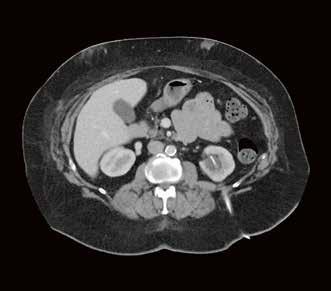

Fall 3:

Thorax-CT im Rahmen einer Lungenkrebsfrüherkennungsstudie. Die Voruntersuchung lag als externe kontrastmittelgestützte Thorax-CT vor. Bei der dosisoptimierten Low-Dose-CT liegt die Strahlenexposition nur noch im Bereich von zwei konventionellen Röntgenaufnahmen des Thorax, die Bildqualität ist für die Fragestellung nach Herdbefunden aber dennoch eindeutig ausreichend, selbst interstitielle Lungenveränderungen lassen sich hier noch beurteilen.

Prof. Dr. med. Johannes Weßling Zentrum für Radiologie, Neuroradiologie und Nuklearmedizin Abb. 3 a: kontrastmittelgestützte Thorax-CT, externe Untersuchung; DLP 216,0 mGy × cm / 3,9 mSv. Abb. 3 b: dosisoptimierte Low-Dose-Thorax-CT, Canon Aquilion Prime SP, Rekonstruktion: AiCE; DLP 13,9 mGy × cm / 0,25 mSv.